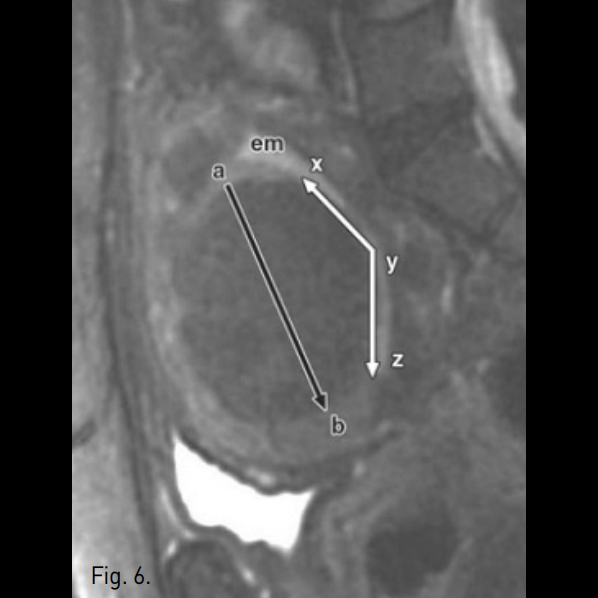

Fig. 6

Baseline sagittal fat suppressed fast spin-echo T2-weighted MR image shows calculation of interface of fibroid with endometrium(em) (xy+yz=xz) and maximum submucosal fibroid dimension (ab). Interface-dimension ratio calculated by (xz / ab).

Sachit 등은 MRI에서 자궁내막에 맞닿은 면적과 자궁근종의 부피간의 비로 endocavitary를 예측하였다 (점막하 자궁근종에서 interface-dimension ratio가 0.55 이상일 때 자궁동맥 색전술 후 endocavitary가 잘 발생한다고 제안함, p<0.005, Fig. 6). 그들은 endocavitary된 경우의 대부분은 시술 전에 점막하 자궁근종(submucosal fibroid)이였으며(13/39, 33%), 근육내 자궁근종(intramural fibroids)의 경우는 일부에서만 시술 후 점막하 자궁근종(submucosal fibroid)이 되었고(2/49, 4%) endocavitary를 보였던 경우는 없었다. 이 공식을 이 증례에 적용하면 처음으로 찍었던 MRI에서 interface-dimension ratio는 거의 1에 가깝다(xy + yz : ab = 6.7 : 6.0= 1.11). 시술 후 시행한 MRI상 자궁근종이 자궁내강 쪽으로 더 돌출되는 양상으로 보여 interfa ce-dimension ratio가 더욱 증가하였다(xz : ab = 8.3: 5.5 = 1.45). 실제로 이 환자에서 색전술 후 endocavitary가 발생하였다. 따라서, 자궁근종의 내막과 맞닿는 면(interface)과 자궁근종의 직경(dimension)의 비가 0.55를 넘는 점막하 근종은 자궁근종의 색전술 후 endocavitary 발생을 예측 할 수 있을 것으로 판단하였다.